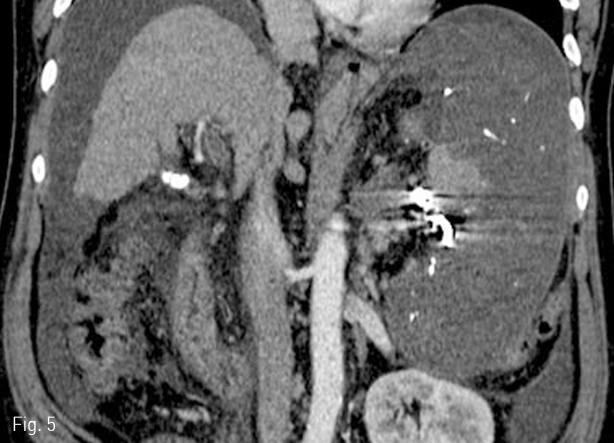

환자는 색전술 후 백혈구 수치가 상승하고 발열증상이 있었으나 보존적 치료 후 완전히 회복되었다. 1개월 뒤 시행한 복부 전산화 단층촬영에서 hilum주위의 일부 비장 실질을 제외한 비장의 대부분의 경색이 초래되었다 (Fig. 5). 색전술을 시행하고 2주 후에 혈소판 수치는 정상범위 내로 증가되었고 이후 12개월까지 유지되고 있다.

Fig 5

Follow-up CT scan obtained 1 month after embolization shows splenic infarction except small portion of the splenic parenchyma.